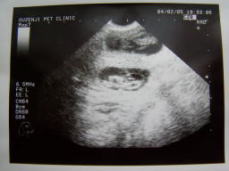

エコー検査を受けに病院に行ってきました。結果はおめでたでした!!モモの子宮には予想以上(5頭近く)の赤ちゃんがいました。2cm弱の赤ちゃんは羊水に包まれ心臓が動いるのが分かりました。一安心です。エコーの写真を見るとにんまりしてしまいます。今日の食事は完食。大好きな馬肺を細かく切ってごはんに混ぜてみた。病院で測ったモモの体重:5kg

この写真は2/5に病院からいただいたエコーの写真。片方の子宮内です。

ちいちゃなモモの子供が2頭いるのが分かります。羊水の中でお腹から出るのを待っています。このエコーの写真から5日経ちましたが今はどのくらいの大きさに成長しているのかな。